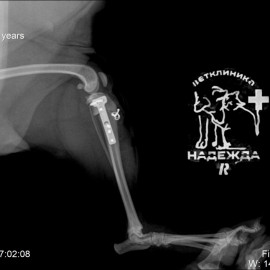

К нам в клинику обратились с жалобой на хромоту на правую заднюю конечность. Беспокоило в течение нескольких дней. После проведенных исследований поставлен диагноз: остеоартрит правого коленного сустава, пателлярный вывих коленного сустава, разрыв передней крестообразной связки. Была проведена операция TPLO, латеральная транспозиция шероховатости правой большеберцовой кости.

Снимок 1 до операции.